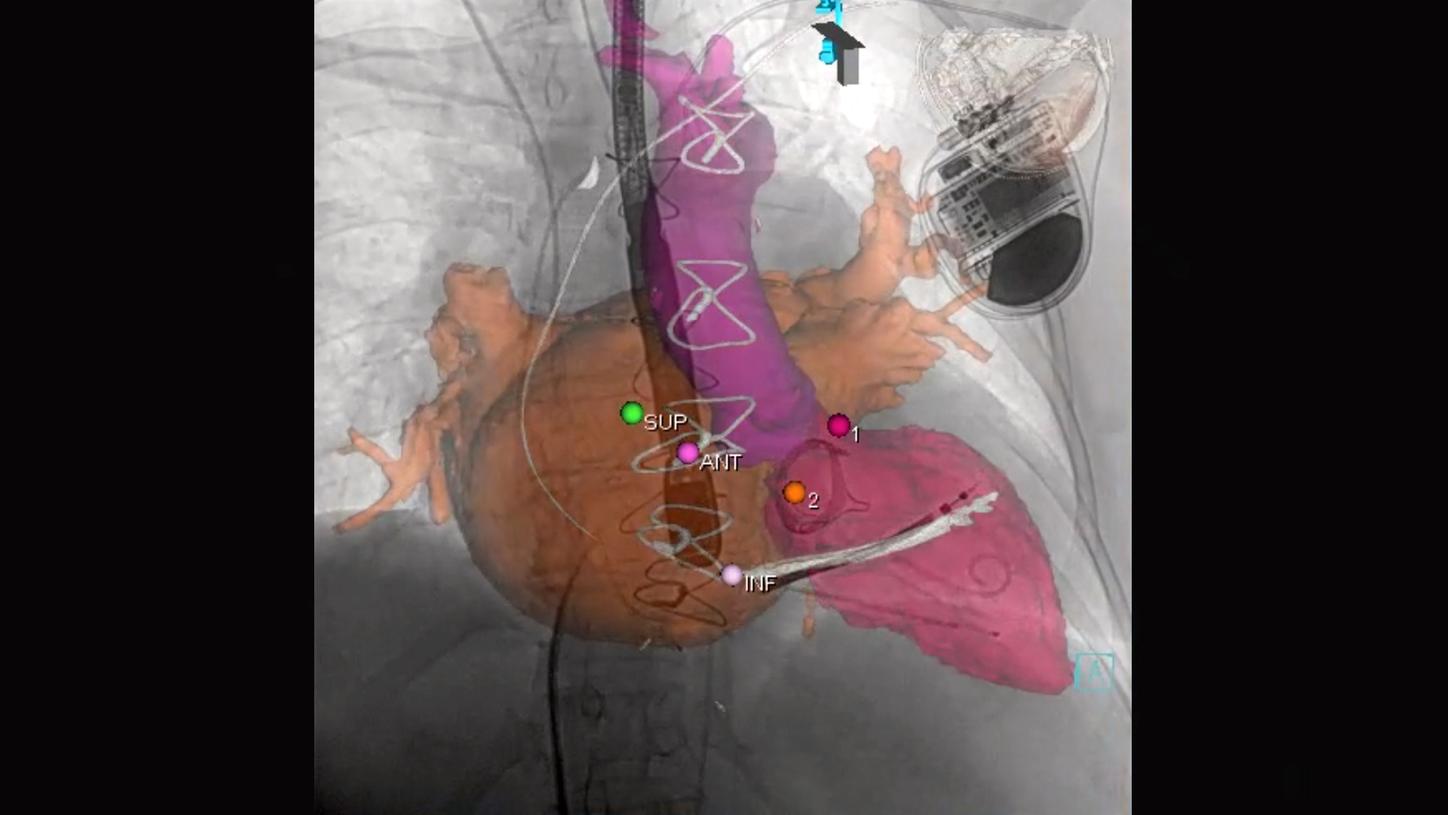

Image guided therapy with fewer manual steps

For each procedure step you can combine a multitude of system settings and turn them into a time-saving, individualized Case Flows, available with one click.

Set the system to the requirements of each procedure step once in terms of C-arm position, angulation and SID, imaging parameters and zoom, display layout and input selection and others.

With Case Flows you can activate these settings with a single touch and thereby eliminate up to six manual system interactions.

Material-specific imaging with Structure Scout

Structure Scout enables improved device visibility supporting ALARA dose due to material-specific optimization of imaging parameters.

With new devices and new materials appearing all the time, image-guided therapy is facing new challenges. Structure Scout adjusts the X-ray spectrum to material-specific acquisition parameters and optimizes visibility of materials, devices, vessels, and background structures independent of procedure or material type with our embedded structure-sensitive algorithm.

Precise system movements

Precision is key to improve the workflow in complex procedures. The reuse of vessel maps for DSA and 3D Roadmap even after C-arm and table movements speeds up the intervention and reduces dose and use of contrast media. ARTIS icono supports this with a (re)positioning accuracy of better than 0.5 mm.